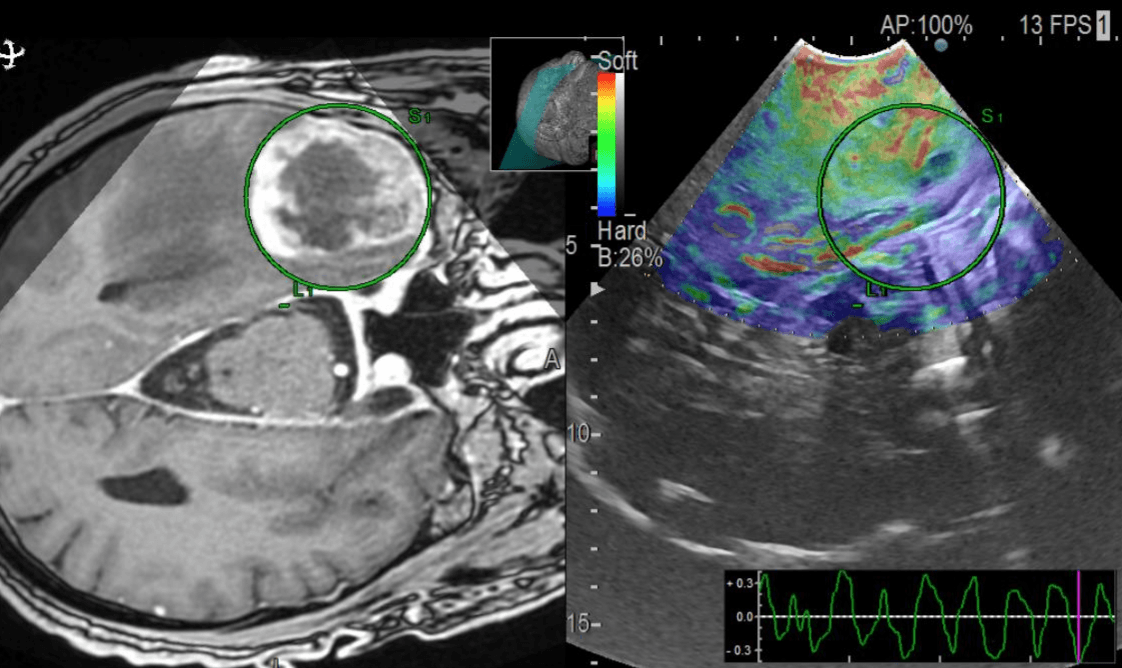

The project aims to analyze intraoperative ultrasound images of glioblastomas and develop new prediction survival models through advanced neuroimaging processing techniques and machine learning algorithms. To collect data, we promoted the creation of the first international database of intraoperative ultrasound images of brain tumors (BraTioUS-DB), in which we will collaborate with at least 6 other hospitals. At the moment we are awaiting the IRB approval of the participating centers, being the first to obtain it the Fondazione Istituto Neurologico Carlo Besta, Milano, Italy.Nuevo párrafo

Predicting the survival of patients diagnosed with glioblastoma (GBM) is essential to guide surgical strategies and subsequent adjuvant therapies. Intraoperative ultrasound (ioUS) is a low-cost, versatile technique available in most neurosurgical departments. The images from ioUS contain biological information possibly correlated with the tumor's behavior, aggressiveness, and oncological outcomes. Today's advanced image processing techniques require a large amount of data. Therefore, we propose creating an international database aimed at sharing intraoperative ultrasound images of brain tumors. The acquired data must be processed to extract radiomic or texture characteristics from ioUS images. The rationale is that ultrasound images contain much more information than the human eye can process. Our main objective was to identify a relationship between these imaging characteristics and overall survival (OS) in GBM. The predictive models elaborated from this imaging technique will complement those already based on other sources, such as MRI and genetic and molecular analysis. Predicting survival using an intraoperative imaging technique that is affordable for most hospitals would greatly benefit patient management.